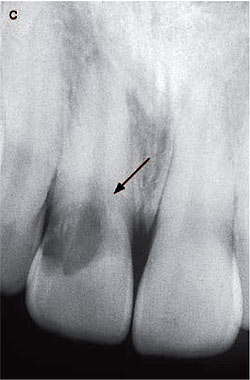

Fig. 5. (a) Radiograph of the maxillary central incisors of a 22-year-old

male. Extensive radiolucent areas extend close to the pulp spaces. Although

similar in appearance to carious lesions, the margins are somewhat irregular.

The pulp space is bordered by a radiopaque line which is more evident in

the right incisor. The invasive cervical resorptive lesion is classified

Class 2. (b) Palatal surfaces of the maxillary central incisors. Pinkish

area are visible near the mesial cervical regions, particularly evident

in the right incisor. From (1). Reproduced with permission from Quintessence

Publishing.